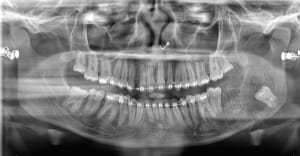

20-04-2021 Panoramique Début.JPG